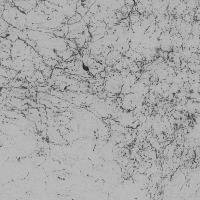

dopamine_th Computer Vision Project

The provided information seems to be insufficient to provide detailed use-cases. The model name, "dopamine_th" implies a possible connection to neurobiology, specifically, to dopamine neurotransmitters. Yet, the "th classes including th" part is unclear, as "th" is not a known term in either computer vision, biology, or bioinformatics domain. It might be a reference to certain classes in your data set, but without further context or clarification, it's challenging to provide accurate use cases. The image of a grey background also doesn't provide significant context. Could you please provide further details concerning this "th" term and more context related to the computer vision model?